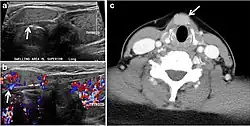

Fig. 7. A 51-year-old female patient post total thyroidectomy for PTC with elevated thyroglobulin measurement. an Axial non-enhanced CT scan of the neck at the level of the thyroid bed demonstrates a well-defined, rounded, homogenously dense soft tissue situated between the trachea and left internal jugular vein (white arrow). b Transverse ultrasound image of the neck demonstrates a well-defined, homogeneous, hypoechoic soft tissue nodule measuring 6 mm (white arrow) with no detected micro-calcifications. Biopsy showed a predominantly residual normal thyroid tissue with micro-foci of PTC.[1] -

Fig. 8. A 48-year-old male patient post total thyroidectomy with PTC recurrence. a Transverse greyscale ultrasound of the neck demonstrates a left thyroid bed heterogeneous, predominantly hypoechoic irregular lesion with calcifications (white arrow). b A spot image of iodine 123 total body scan of the neck demonstrate a focus of abnormal radiotracer uptake at the left thyroid bed (Black arrows) between the annotated markers. c Enhanced axial CT scan of the neck demonstrates an enhancing large left thyroid bed mass (white arrow) with no calcifications. The lesion exerts a mass effect on the oesophagus (black arrow) and is inseparable from the trachea.[1] -

The likelihood of positive anatomic imaging is greater when serum Tg is >10 ng/mL. A diagnostic CT scan adds additional value to neck US in detecting central compartment macro-metastases in the mediastinum and retro-tracheal area. According to the recent American Thyroid Association guidelines, an upper chest and neck CT scan with IV contrast should be obtained when: 1) neck US is inadequate in visualizing possible local nodal disease (high Tg, negative neck US, and RAI imaging); 2) US is not able to delineate the disease completely, as in the case of bulky recurrent nodal disease; or 3) evaluation of possible recurrent invasive disease is needed (Figs. 7, 88 and and9).9). CT scans are also the most sensitive diagnostic tool for the detection of pulmonary micro-metastases. Many of the neck US features that are considered as suggestive signs of disease recurrence are also applicable to CT examination. These signs might include sizable rounded nodules in the thyroid bed, fine calcifications, or cystic change.[1]